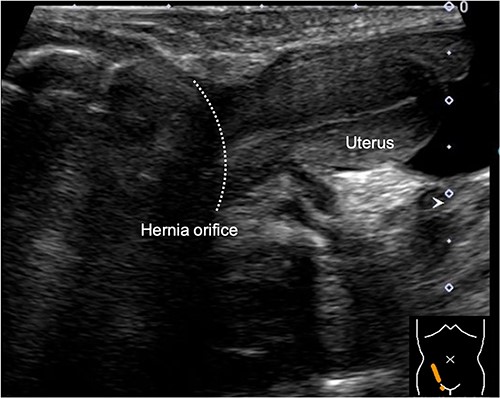

When the patient turned 1 year old, a laparoscopic percutaneous extraperitoneal closure (LPEC) procedure was carried out to address the bilateral inguinal hernias. Although the uterus was slightly deviated toward the right side of the pelvis, its position appeared to make it difficult for the uterus to herniate through the hernia orifice. The right fallopian tube was located near the hernia orifice, and a high ligation was carefully performed to avoid entanglement of the fallopian tube (Fig. 3). The procedure was concluded successfully without any significant complications. Subsequent follow-up examinations conducted after one year showed no recurrence of the inguinal hernia.

Findings during laparoscopic inguinal hernia repair (Laparoscopic Percutaneous Extraperitoneal Closure: LPEC) conducted at the age of 1 year. (A). Preoperative observations: The patent right inguinal hernia orifice was confirmed. The uterus and fallopian tubes were located close to the hernia orifice, but there was no evident protrusion, and the uterus was not in a position to prolapse. (B). Postoperative observations: High ligation was safely performed, with special attention given to the fallopian tubes.